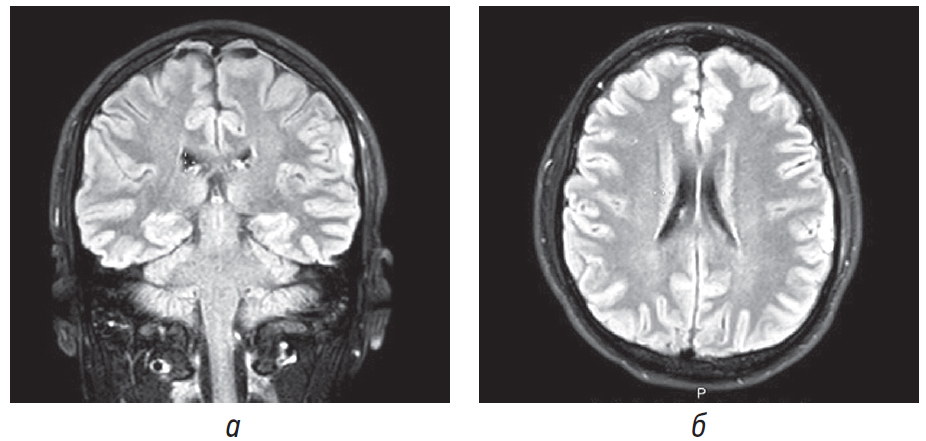

Fig. 1. Patient L. MRI of the brain — on coronal (а) and axial sections (б) (FLAIR mode) the area of contusion in the subcortical-cortical area of the left parietal lobe measuring up to 14 × 6 × 9 mm. Before the MRI, the patient had been treated for 6 days with a diagnosis of traumatic brain injury — brain commotion. According to CT of the head on the 3rd day after the injury, no structural disorders were detected

Рис. 1. Пациент Л. МРТ головного мозга — на корональном (а) и аксиальном срезах (б) (режим FLAIR) картина участка контузионных изменений в субкортикально-кортикальных отделах левой теменной доли размерами до 14 × 6 × 9 мм. До проведения МРТ пациент в течение 6 дней проходил лечение с диагнозом ЗЧМТ, СГМ. По данным КТ головы на 3-й день после травмы структурных нарушений выявлено не было